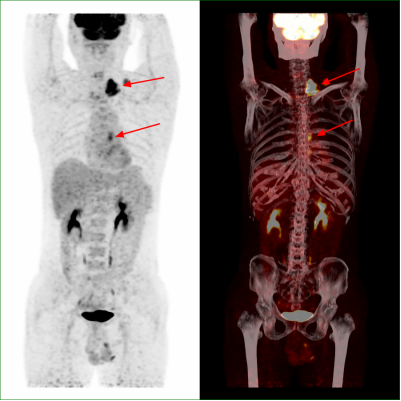

近期,在外务工的市民何先生无意间发现自己左颈部出现有肿块,随后去到当地医院检查,超声提示其左颈部有一个4.9厘米×2.9厘米的包块,彩超提示为:双侧颈部多发淋巴结。为得到进一步诊断和治疗,何先生选择回到了自贡,在市四医院进行PET/CT检查提示为食管癌伴颈部纵隔淋巴结转移。随后,医务人员为其进行胃镜下活检,明确为食管鳞癌。病情得以明确后,何先生在市四医院得到了妥善的治疗。

近期,李女士在体检时发现,其肺部存在一个直径约1.1厘米的压实性结节影,并且该结节形态欠规则,边缘模糊。当地医院临床医生高度认为该结节为恶性肿瘤。吓坏了的李女士为得到准确诊断,来到了市四医院核医学科进行了PET/CT检查。对照PET/CT图像,医务人员仔细辨别后,认为其为炎性病变。后经病理检查,证实了医务人员的判断。看到恶性肿瘤被排除的检查结果,压在李女士心头的大石头总算落了地。

PET/CT是一种既具有PET能量代谢功能,又兼顾CT解剖成像两种设备优势融合的高端显像设备,通过PET/CT不仅可以评估原发病灶,同时可以了解全身情况,有利于制定最佳治疗方案,具体优点如下:

4.一次注射显像剂后亦可完成全身检查,不仅可以发现全身疾病,若在其他位置发现原发灶,还可通过PET/CT全身大范围寻找转移灶,如卵巢癌,颈部淋巴结转移等。